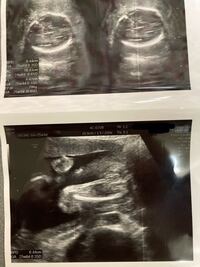

赤ちゃんの性別わかる方いたら教えてください 25週目の検診の時のエコー Yahoo 知恵袋